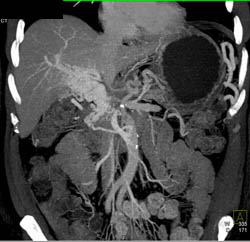

Focal Nodular Hyperplasia (FNH)